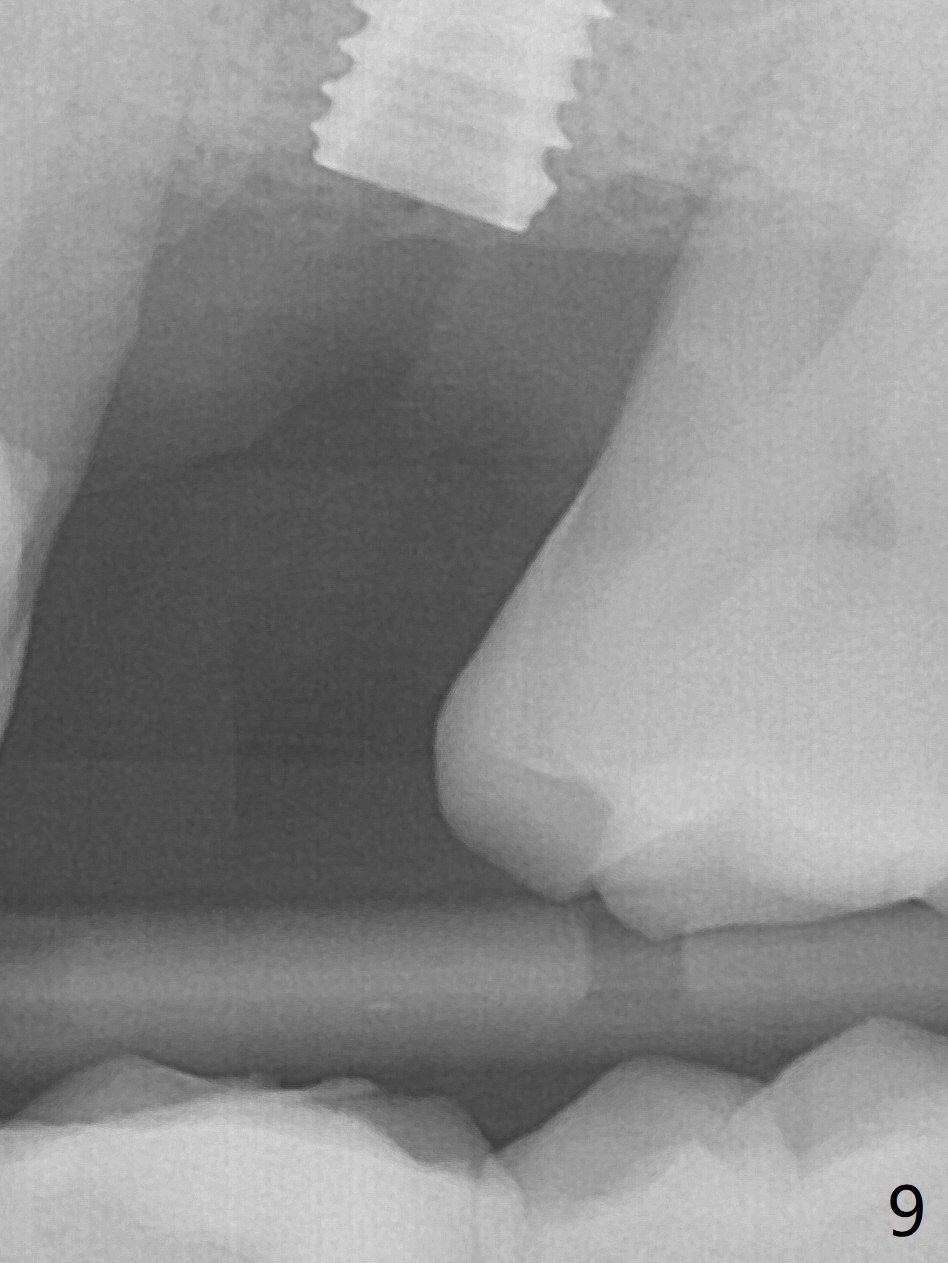

Trajectory of sinus lift without guide at #14 is off (Fig.1 (Magic Sinus Lifter (L) for 9 mm (gingival level)) and needs to be corrected (Fig.2 long line) by re-using 4.8 mm Magic Drill. Following placement of PRF membrane and Demineralized Cortical Allograft (.125-.850 mm) for sinus lift (Fig.3 black dashed line), a 4x10 mm dummy implant is placed with off trajectory. The latter will be fixed by using Lindmann bur to remove the bone distal (Fig.4). The result is less satisfactory with placement of 4.5x10 mm dummy implant (Fig.5). It appears necessary to initiate a new osteotomy (Fig.6 long black line). In fact the result is appealing (Fig.7). The final implant (5x7.3 mm) seems to be placed ideally shown by PA (Fig.8) and BW (Fig.9). Immediately postop CT demonstrates distal defect (Fig.10 *;3-D) and supracrestal placement palatal (Fig.11 P; coronal section). More allograft is then placed in these 2 areas. In all, it is difficult to establish a correct osteotomy without guide. The patient return for uncover 3.5 months postop, although there is a small hole in the middle of the incision (Fig.12). The crown/abutment becomes loose less than 1 month post cementation when the patient chews something tough. It is more related to the unfavorable implant/crown ratio. It is loose again 2 months later. Screw driver is buried inside the abutment with plumber tape. When it is loose for the 3rd time 13 months post cementation, the existing screw driver with a created slot (for retention) is buried without plumber tape after retorque at 35 Ncm (Fig.13). A tissue-level implant should have been used.